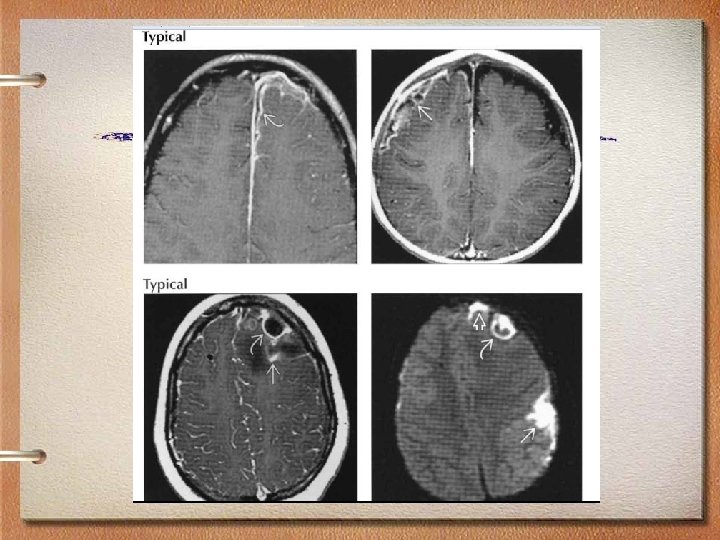

MRI findings • Imaging varies with stage of abscess development • Early capsule: Well-defined, thin-walled enhancing rim • Ring-enhancing lesion with high signal • T 2 hypointense abscess rim with surrounding edema • Typically supratentorial • Frontal and parietal lobes most common, gray-white junction (hematogenous)